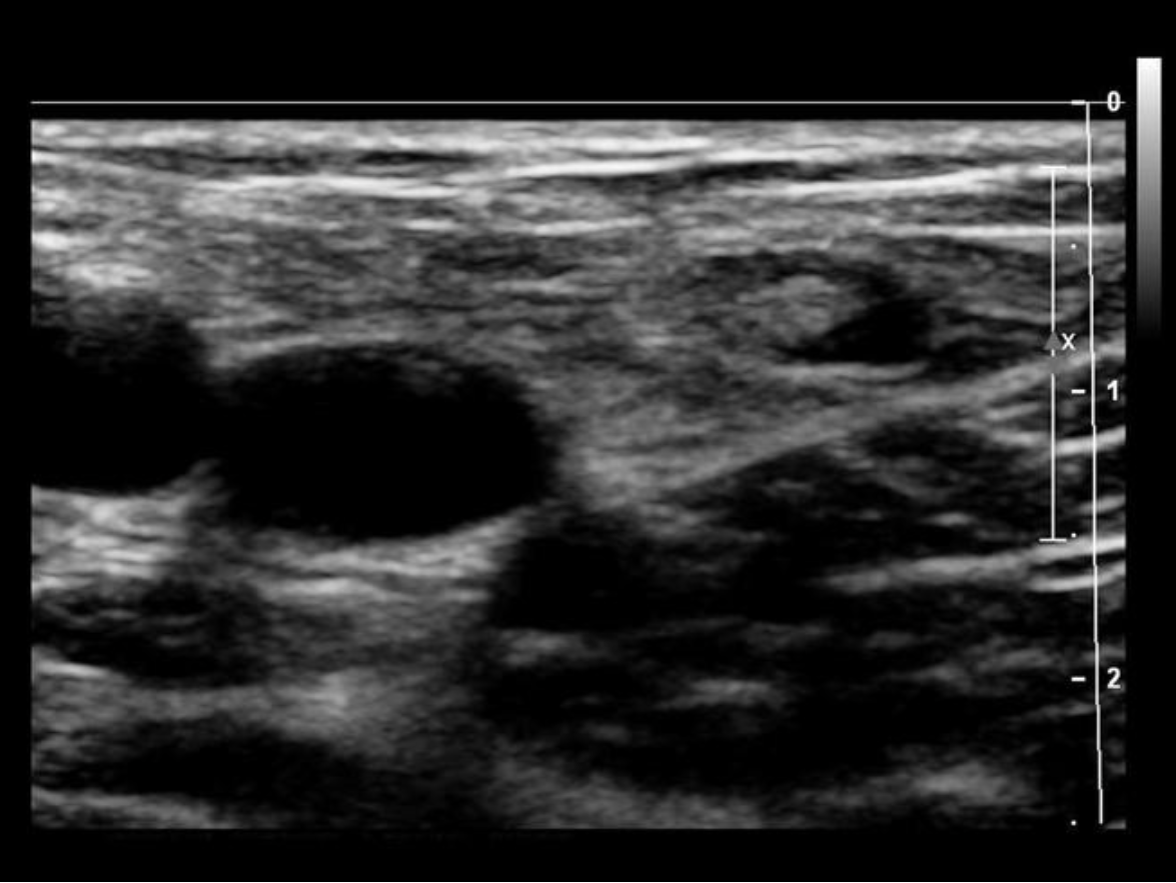

Which of the following is a characteristic of a normal lymph node?

A. posterior enhancement

B. round shape

C. thin hypochoic rim with hyperechoic central hilum

D. thick hypochoic rim with hypervascularity

Normal lymph nodes are ovoid in shape. They do not demonstrate posterior enhancement. As lymph nodes enlarge with abnormal fluid accumulation, they appear more rounded and hypochoic/anechoic. The "plump" cortex causes decreased visualization of the central hilum. Color Doppler can be used to locate the hilum and main vascular supply. Posterior enhancement is present in structures posterior to abnormal nodes with significant fluid accumulation.

While scanning the thyroid, you identify a 0.6cm ovoid structure outside the thyroid, lateral to the left carotid artery. The structure has a thin hypoechoic rim surrounding a hyperechoic center. These findings are most suggestive of:

A. thyroglossal duct cyst

B. parathyroid carcinoma

C. normal esophagus

D. normal lymph node

Normal lymph nodes are ovoid in shape. They do not demonstrate posterior enhancement. As lymph nodes enlarge with abnormal fluid accumulation, they appear more rounded and hypoechoic/anechoic. The "plump" cortex causes decreased visualization of the central hilum. Color Doppler can be used to locate the hilum and main vascular supply. Posterior enhancement is present in structures posterior to abnormal nodes with significant fluid accumulation.

Find the normal lymph node

A normal lymph node is oval in shape and demonstrates a thin hypoechoic rim of tissue around an echogenic hilum. Abnormal lymph nodes demonstrate a more rounded shape, thickened cortex that can appear anechoic. and there is loss of differentiation of the hilum.